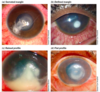

How will somebody with acute angle closure glaucoma present and what will you find on examination?

Presentation (Systemically unwell)

- Severely painful red eye

- Blurred vision

- Halos around lights

- Headache, Nausea, Vomiting (often mistaken for gastroenteritis until you look in their eye)

Examination

- Red eye

- Fixed dilated pupil

- Corneal haze

- Teary

- Decreased visual acuity

- Firm eye on palpation